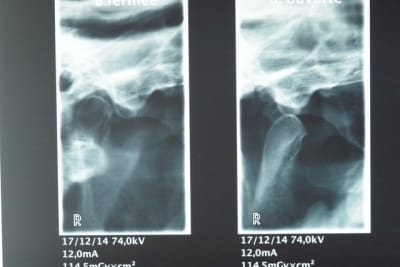

Voilà maintenant les radios:

2° Une radio des ATM D et G bouche ouverte et bouche fermée.

A priori je ne pense pas que ce patient souffre de luxation au vu des radios.

Qu'en pensez-vous ?

Il n'y a pas de luxation, c'est pas une surprise ça se voyait depuis le début.